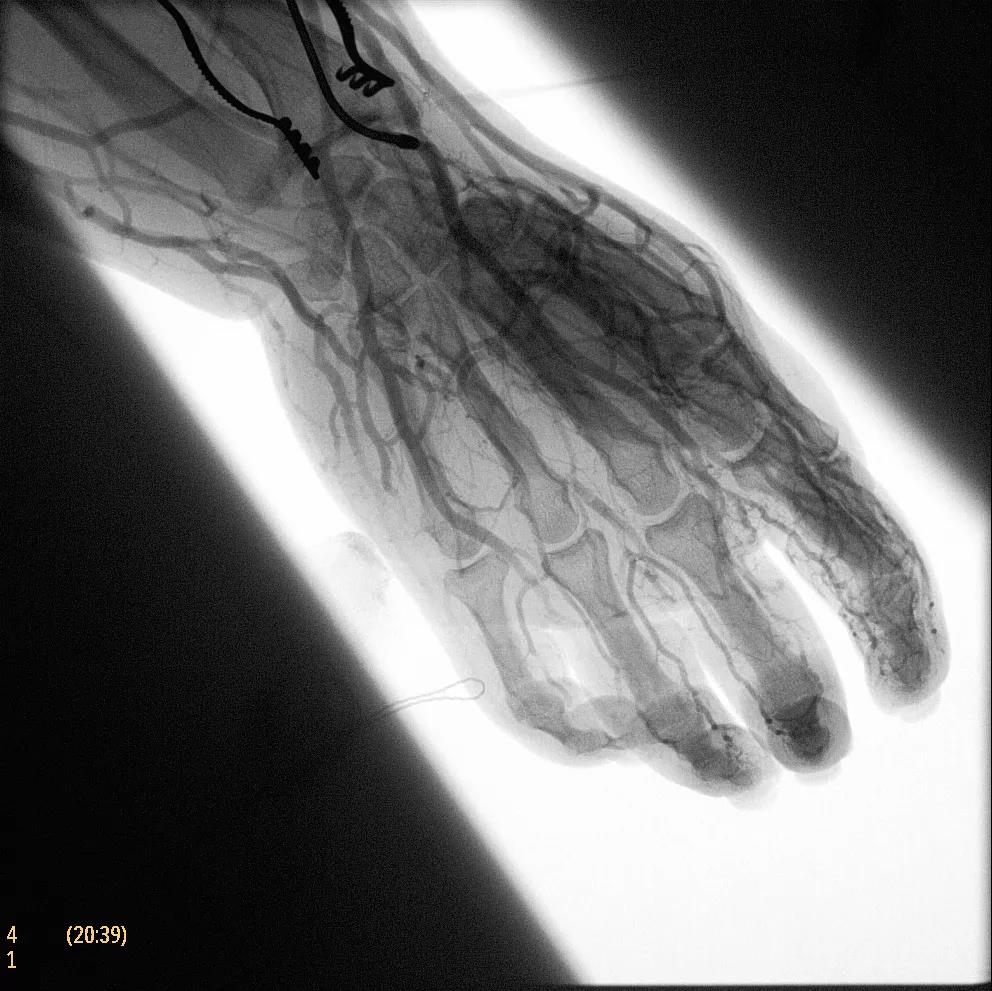

為了獲得清晰的高質量圖像,Zenition 70 采用了與公司Azurion平臺相同的圖像處理算法,可提供患者解剖結構的高清可視化和更大的可視區域。飛利浦的MetalSmart軟件等功能可確保圖像質量,該軟件可自動調整圖像的對比度和亮度,以便在視野中存在金屬物體(如植入物)時提高圖像質量 - 這一特性使Zenition 70在整形外科中特別有用。